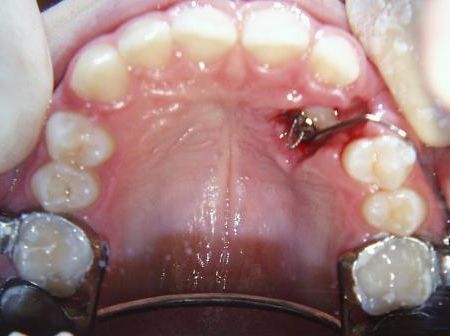

Fallbeispiel 6 zeigt die Einordnung eines gaumenwärts verlagerten linken oberen Eckzahns mittels Lingualapparatur nach chirurgischer Freilegung.

Bild 1: Beginn - Bild 2: nach 6 Monaten - Bild 3: nach 1 Jahr und 9 Monaten